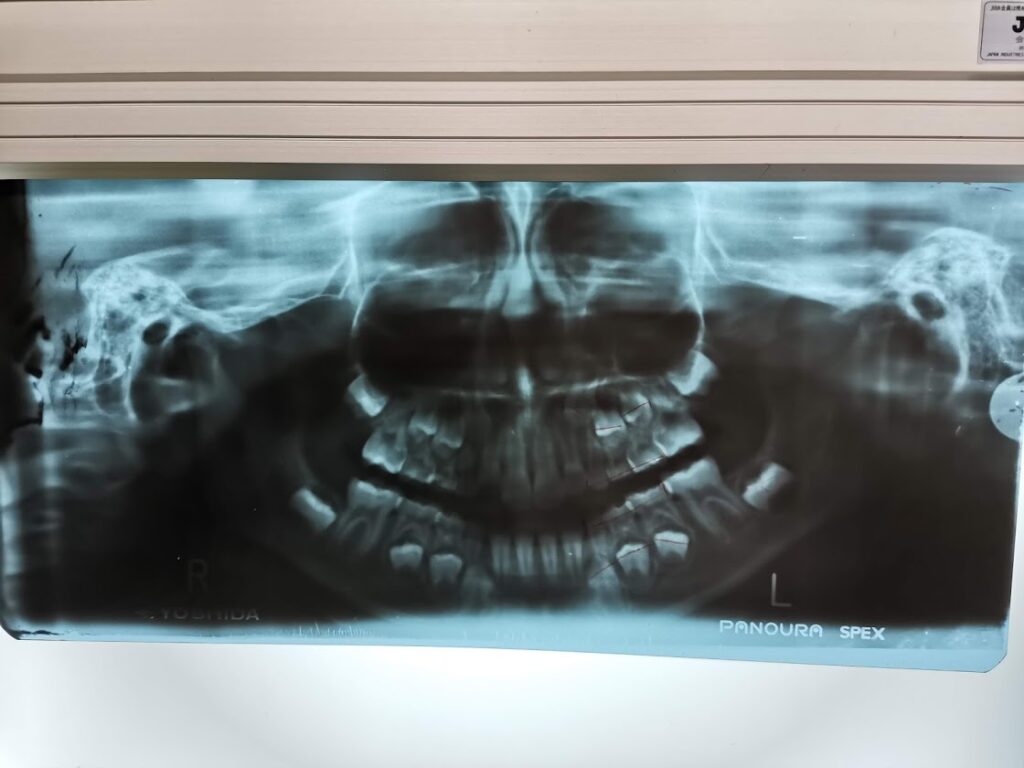

この回は一通り検査ということでしたので、1時間くらいかけてレントゲンをあれこれ撮ったり、歯形を作ったり。